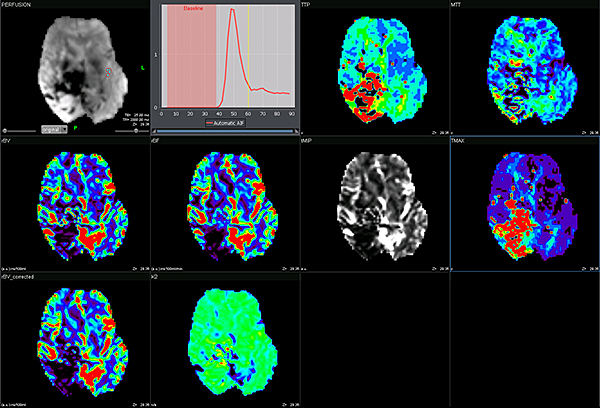

Перфузія DSC Perfusion

Додаток DSC Perfusion обчислює оптимізовані параметричні карти (rBV, rBF, TTP, MTT, TMAX, tMIP) із сирої перфузійної серії та забезпечує алгоритм для корекції ефектів розповсюдження контрастної речовини, обчислюючи карту проникності. Ця програма підтримує нерегулярний вибір часу та складається з наступних модулів: автоматична або ручна обробка arterial input function (функції артеріального наповнення), автоматична сегментація фону, чотири методи деконволюції (sSVD, cSVD, oSVD та байезівський) та алгоритм миттєвої корекції руху.